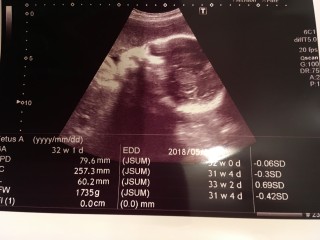

標準より小さいので心配です。 ずっと咳してたから、お腹ん中でストレスだったかなぁ? 去年に3月に流産の子を出産してます。

前回30Wの健診エコーでブチャイクに写った我が娘。今回はエコープラスコンデジで動画撮影。かわいく写って一安心(ToT) ただ…BPD8.6(35W相当)AC27.5(33W相当)FLは31W相当と、頭と胴体はデカく足は短いというタラちゃんのような体型にお育ちになっているようだ…できれば足が長くなってほしいワガママ親心。 推定体重は1964gでした。 母体体重は妊娠前+2.9kgでいい感じだけど足の浮腫みと今回初めて尿蛋白が出てしまった。対策は大概やり尽くしているからこれで悪化して管理入院になったらどうしようとまた別な心配事ができてしまった。